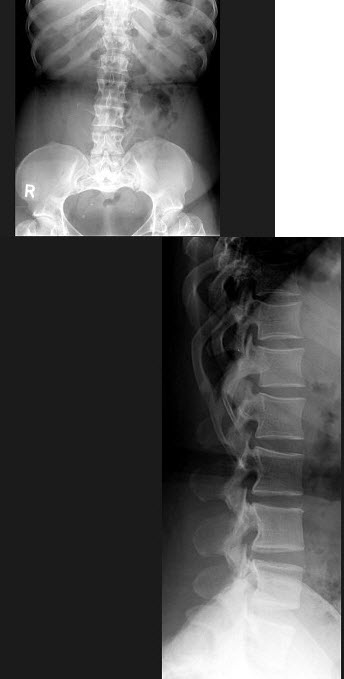

120、单项选择题

男,71岁,背部酸痛,低热,乏力,消瘦2月余,结合影像学表现,最可能的诊断是()

A.脊柱转移瘤

B.化脓性脊柱炎

C.脊椎结核

D.椎体压缩骨折

E.阻滞椎